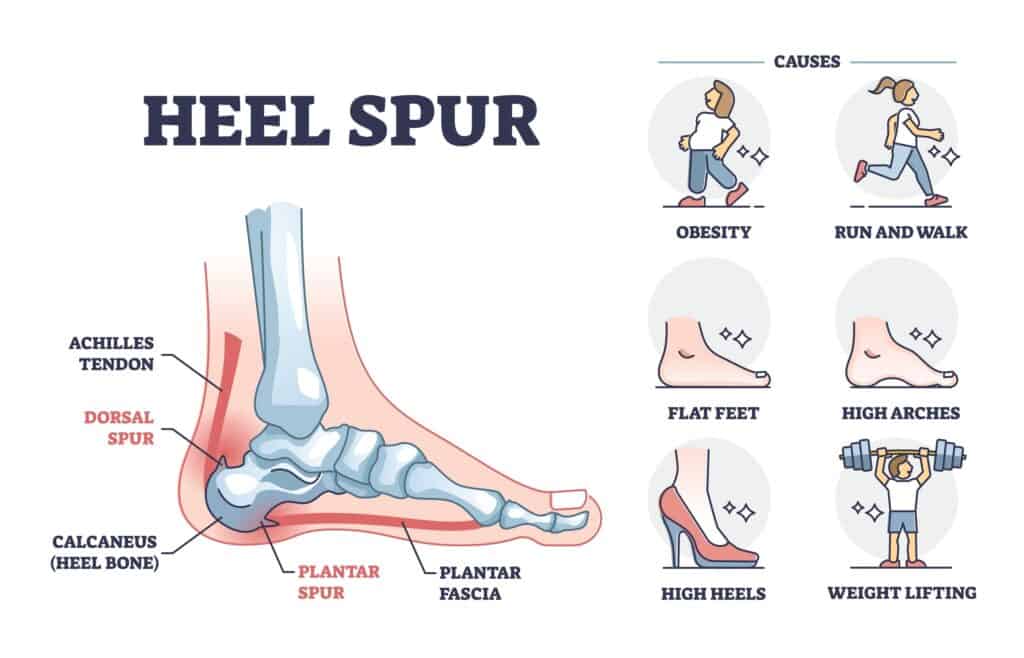

Heel spur PPT